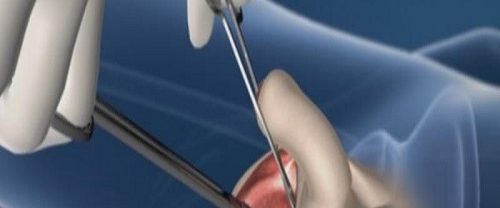

Transfix Tekniği ile Ön Çapraz Bağ Yırtılması ve Tedavi Yöntemleri Transfix Tekniği | Ön çapraz bağ yırtılması, genellikle spor yaralanmaları veya ani dönme hareketleri sonucu ortaya çıkan bir durumdur. Bu yırtık, dizin stabilitesini etkileyebilir ve günlük aktivitelerde ve spor yaparken ağrı ve kısıtlılığa neden olabilir. Ön çapraz bağ yırtılması olan birçok kişi için cerrahi müdahale gerekebilir.…